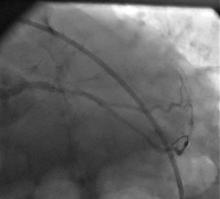

1) LM: subtotal ISR lesion (figure 2, figure 3)

2) LAD: occluded at the ostium and filled via LIMA

3) LCX: proximal non-significant lesion

4) RCA: mild diffuse disease